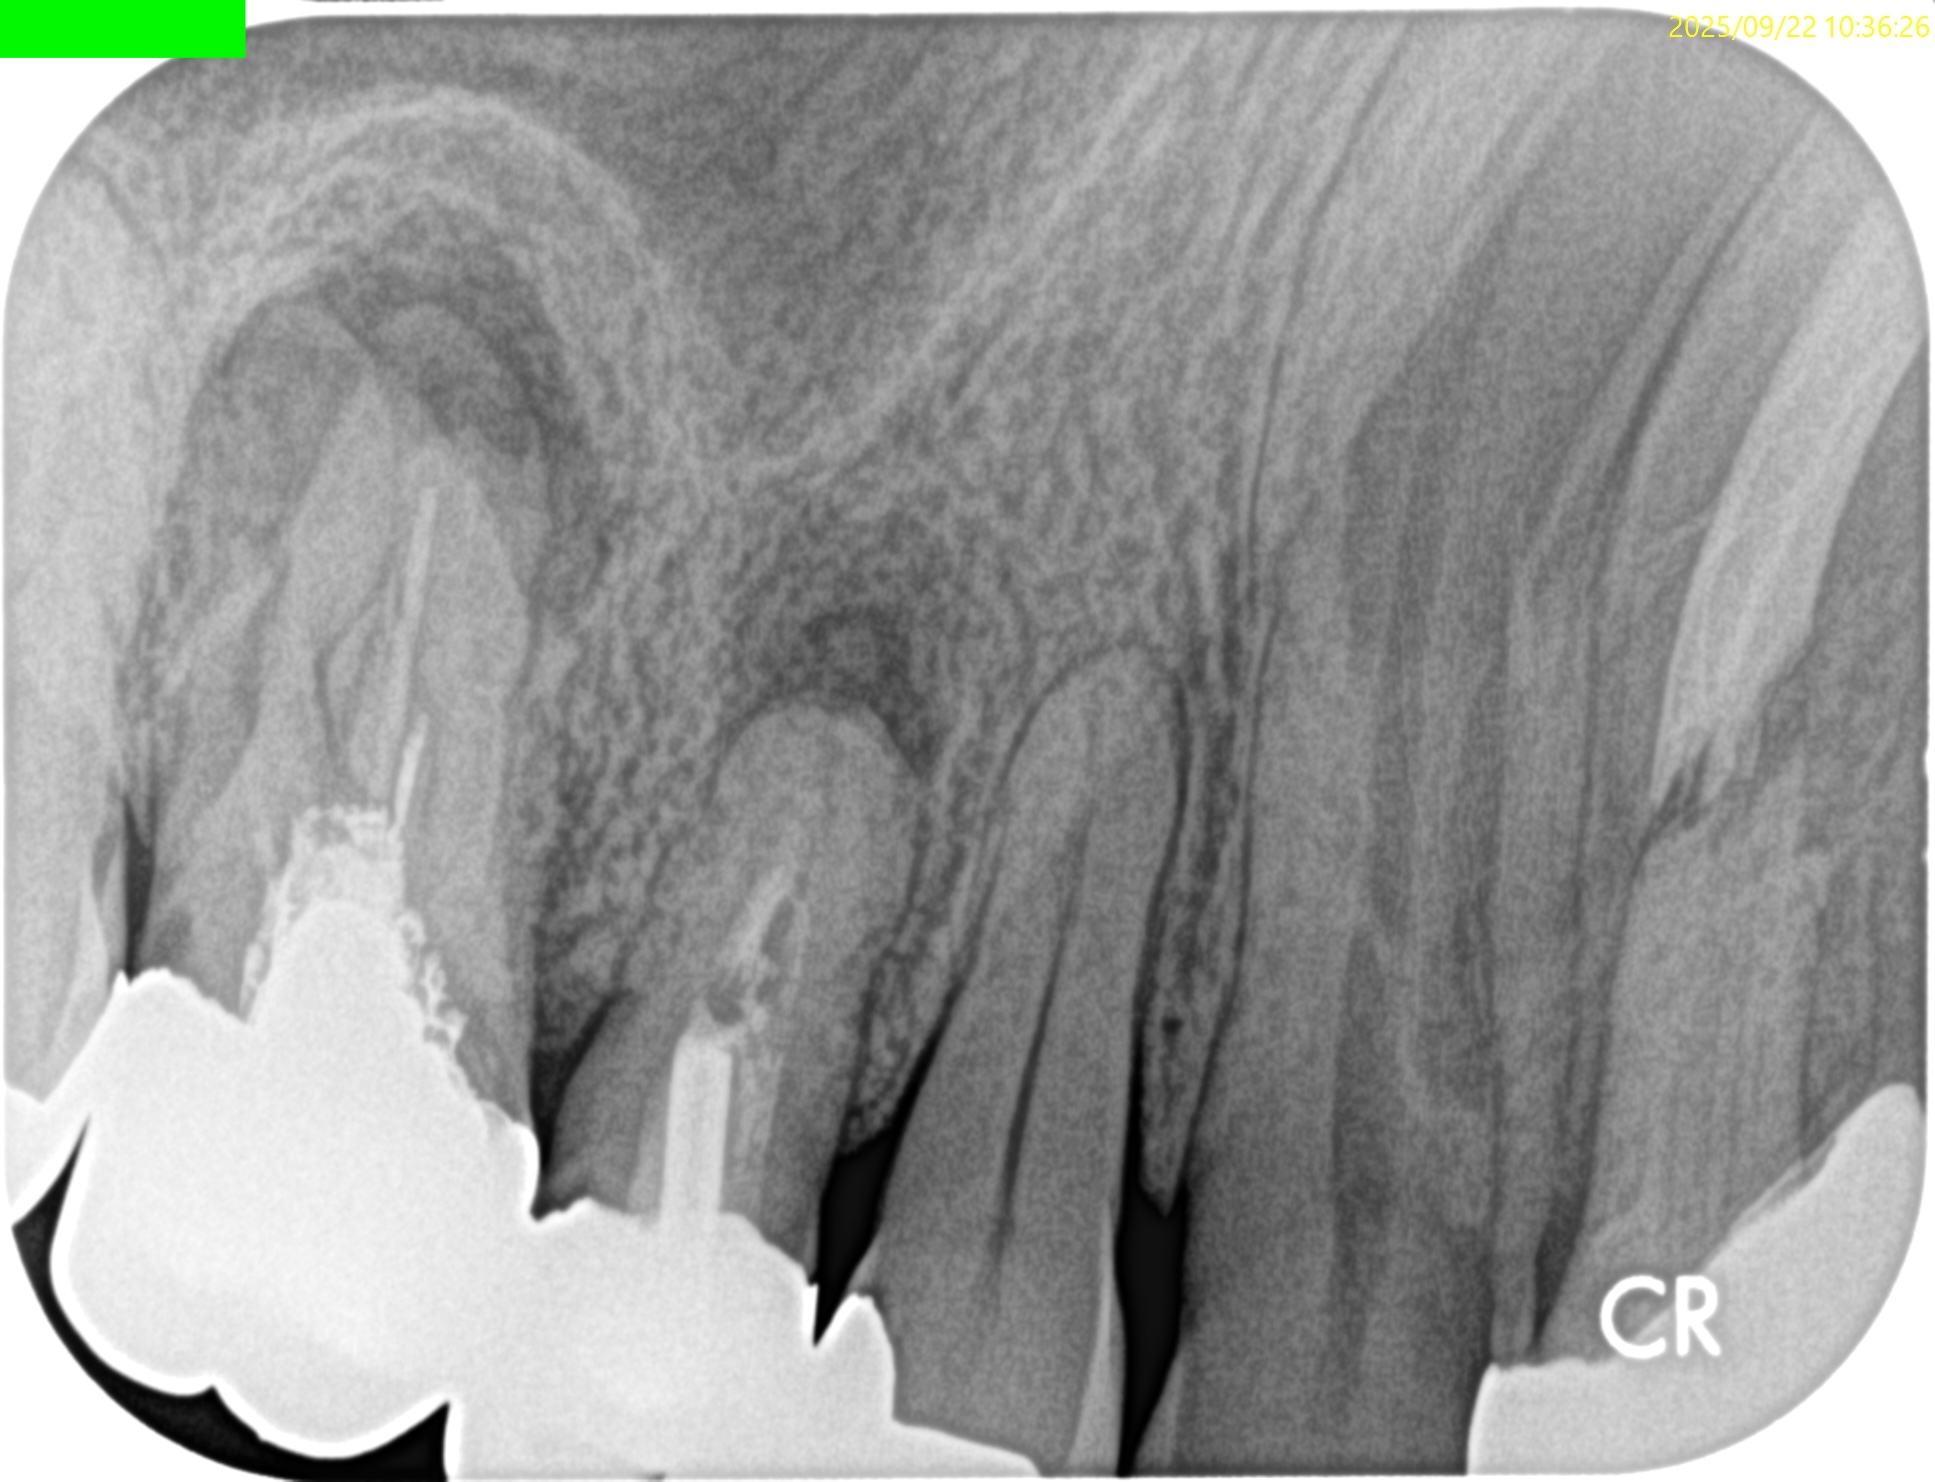

PA(2025.9.22)

これを治療した歯科医師は何もしていないに等しいだろう。

これで抜歯とは…

患者さんが疑念を持って正解だ。